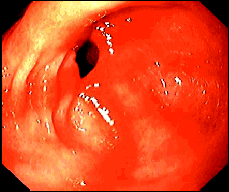

Figura 2. Un caso de ectasia vascular antral gástrica semejando el eritema cofluente al píloro (comb-like erythema)

El diagnóstico diferencial es con el eritema cofluente al píloro (comb-like erythema) (Figura 3), la gastritis hemorrágica y la gastropatía portal hipertensiva. La diferenciación entre el GAVE (Figura 4) y la gastropatía portal hipertensiva es de suma importancia ya que el sangrado de esta última responde al tratamiento con beta bloqueadores. No es infrecuente que al paciente se le hayan practicado varias gastroscopias antes de que el diagnóstico de GAVE sea considerado (Figura 5).

Figura 3. Imagen endosc+opica de un caso de eritema cofluente al píloro (comb-like erythema)